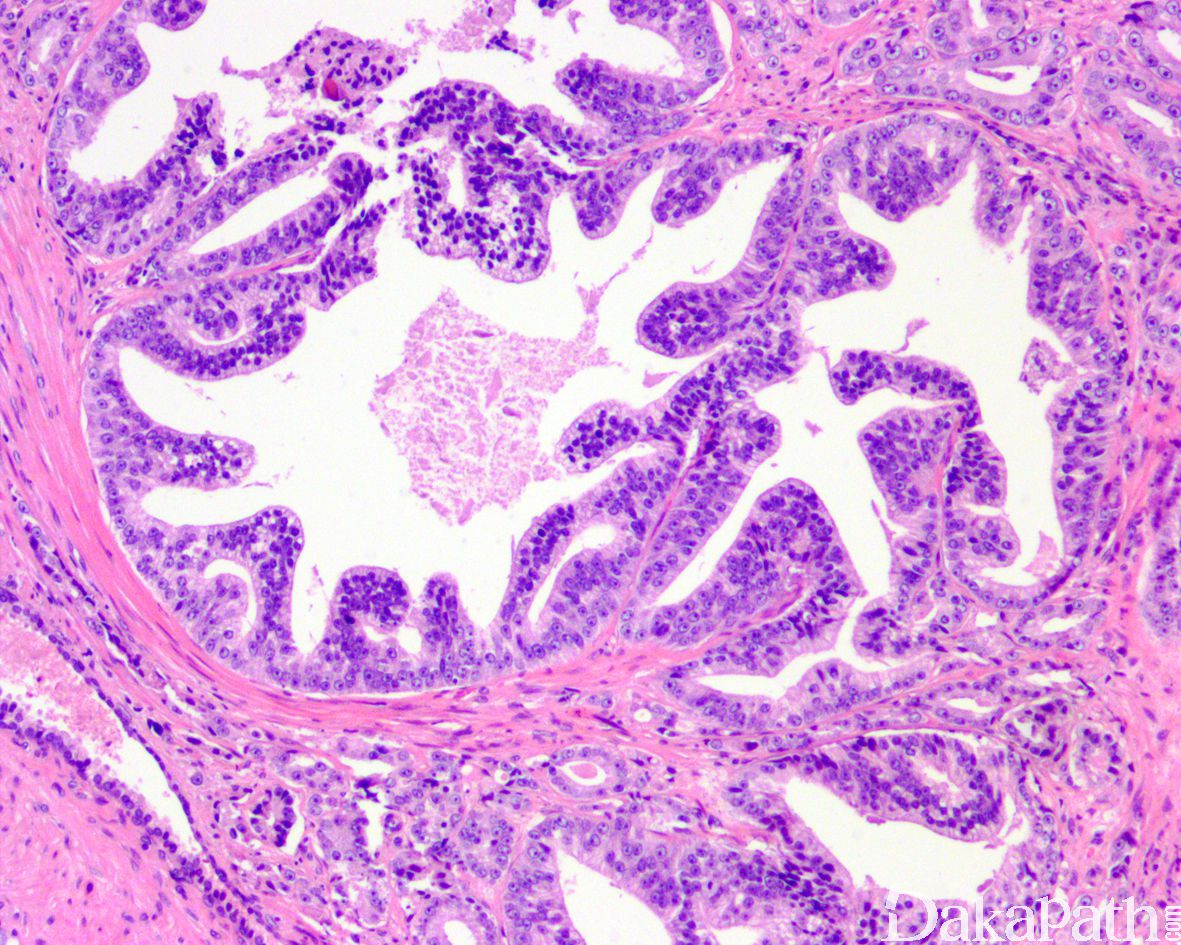

组织学上类似于高级别 PIN 但免疫组化染色显示基底细胞完全缺失;

肿瘤性腺体通常排列密集,呈囊性扩张,被覆上皮呈假复层排列,柱状或圆形,腺腔内瘤细胞呈平坦型、微乳头状、簇状或纤细而薄的长乳头状生长(可见纤细的纤维血管轴心)凸入腔内;

类似于经典型 HGPIN 的 PIN 样腺癌 Gleason 分级为 3 级,腺腔内显示纤细而薄的乳头状生长的 PIN 样腺癌 Gleason 分级为 4 级。